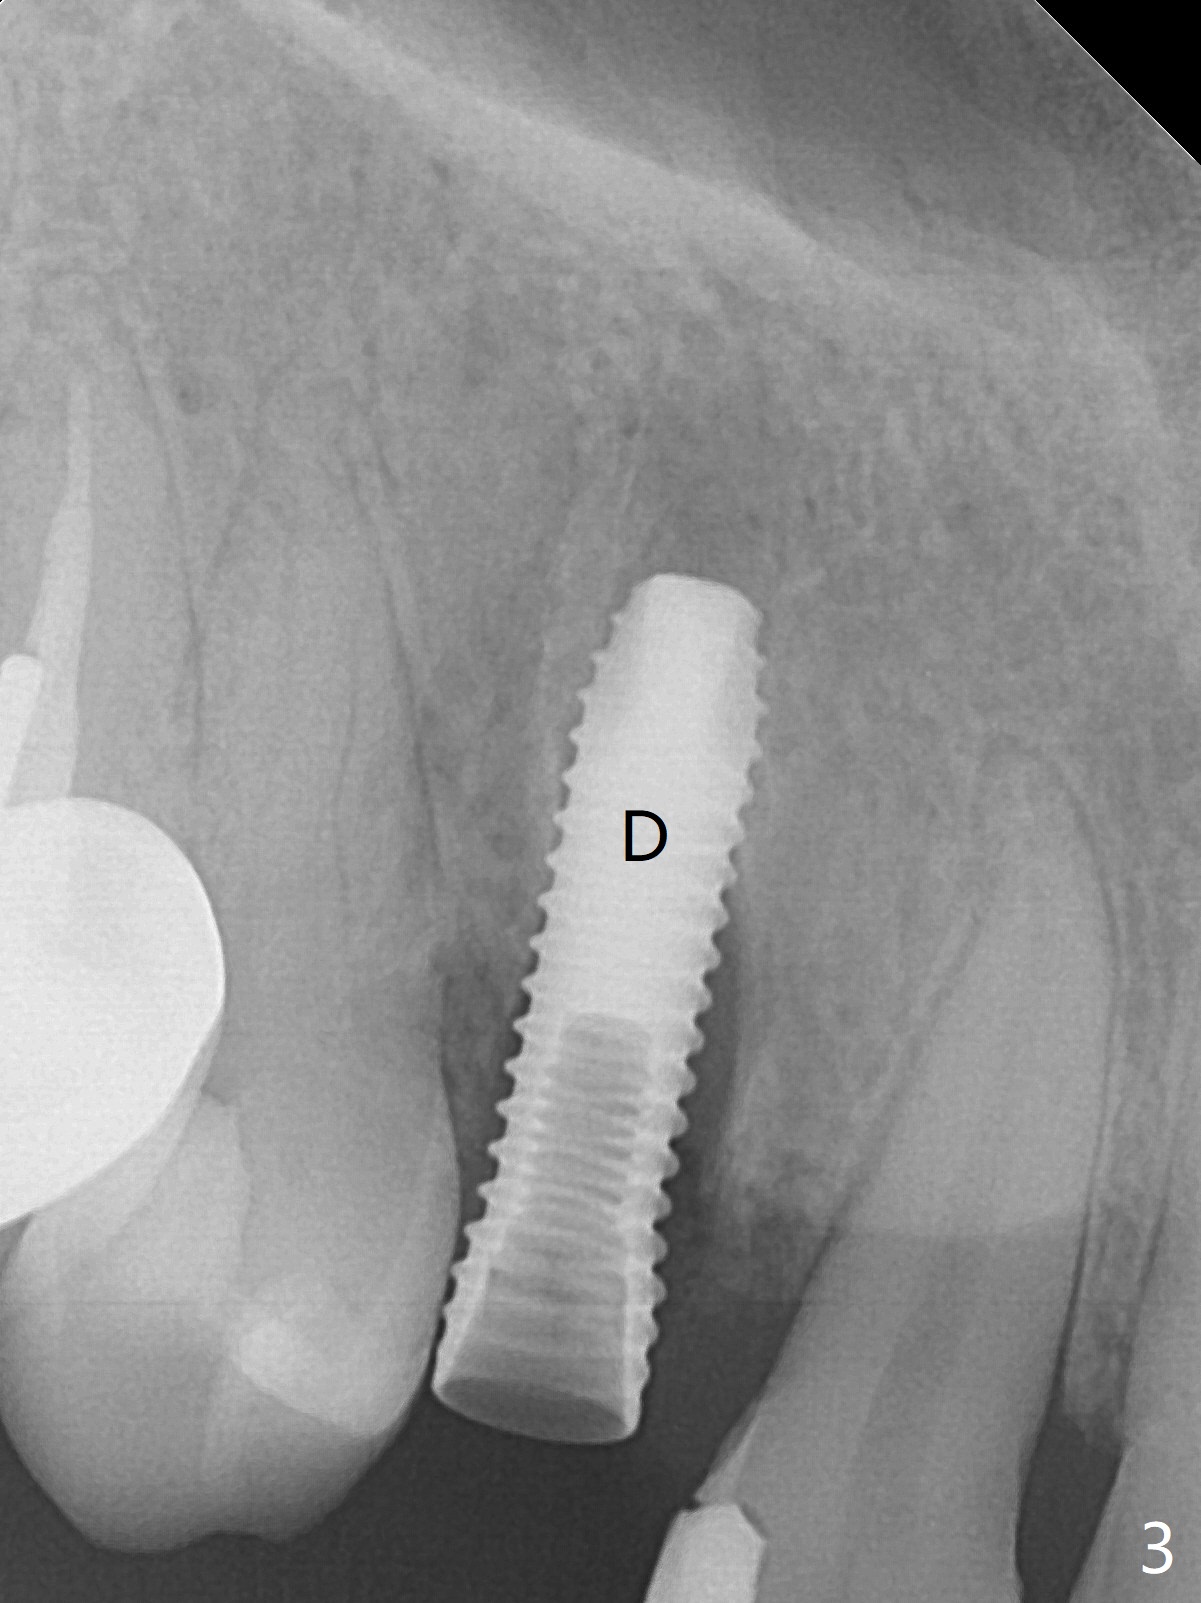

When the tooth #6 with loose crown and post (Fig.1) is extracted, there is no granulation tissue in the socket with the thin intact buccal plate. As planned, osteotomy is initiated in the mesio-palatal slope of the socket (Fig.2 red dashed line). After osteotomy for 3x20 mm (gingival level), a 3.8x15 mm dummy implant is placed partially (Fig.3 D). A final implant with the same dimension is placed with > 50 Ncm (Fig.4). Before and after placement of a 4.5x5(3) mm abutment, Vera graft is placed in the remaining socket space (mainly buccal, Fig.5 *). As routine, an immediate provisional is fabricated with occlusal clearance. The gingiva looks healthy around the provisional 1 week postop (Fig.6 P). Adjust and polish the mesioocclusal composite at #5 if necessary before impression. The bone graft appears to remain in place 4.5 months postop (Fig.7). A bevel buccal subgingival margin is placed prior to impression. The bone density around the coronal portion of the implant increases 9 months postop (4 months post cementation, Fig.8). There is no gingival erythema or edema around the implant crown at #6 ten months post cementation (Fig.6, as compared to preop condition and that of the neighboring crown (*)). Both the buccal and palatal plates are thin or absent 1 year 5 months post cementation (Fig.10,11, as compared to Fig.12 for the tooth #11 (thin buccal bone)). Socket shield should be done with a smaller implant.